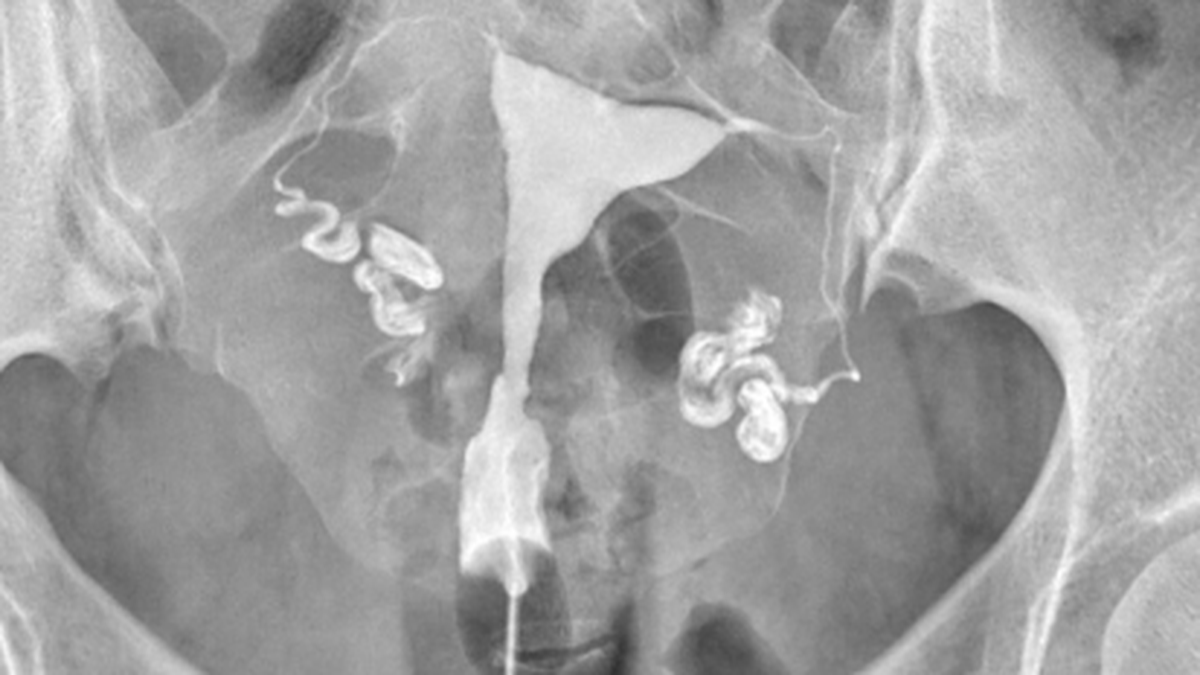

Cet examen consiste à prendre des radiographies du pelvis après injection par le col d’un produit radio‑opaque qui passe ensuite dans l’utérus et les trompes.

Il injecte ensuite doucement un produit radio‑opaque par le col qui va permettre d’opacifier l’utérus, puis les trompes si elles sont perméables. Différents clichés radiographiques sont alors réalisés.

L’hystérosalpingographie permet de vérifier que les trompes ne sont pas bouchées et qu’elles présentent un aspect normal. La principale cause de pathologie tubaire est l’infection. En effet, une trompe qui a été infectée peut garder des séquelles et apparaître bouchée ou dilatées ce qu’on appelle l’hydrosalpinx.